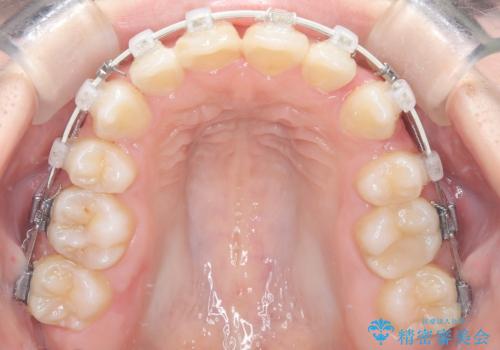

- 前歯のデコボコ(叢生)と、上下の歯が閉じない開口を主訴にご来院されました。精密な検査の結果、歯が並ぶスペースが不足しており、特に奥歯の咬み合わせが安定していないことが開口の原因と判明。患者様と相談し、上下左右の小臼歯を抜歯することでスペースを確保し、審美ワイヤー矯正で全体を整える治療計画を立案しました。これにより、見た目の改善だけでなく、機能的な咬み合わせも獲得することを目指します。

今回の矯正治療では、歯が並ぶスペースを確保するため、上下左右の小臼歯を抜歯しました。装置には目立ちにくい審美ワイヤーを使用し、見た目に配慮しながら治療を進めました。抜歯によってできたスペースを利用して歯を並べ、前歯のデコボコを解消。同時に、歯列全体を動かすことで、上下の歯がきちんと閉じる開口も改善しました。治療期間は約2年間。治療の結果、コンプレックスだった前歯のデコボコと開口が解消され、整った美しい歯並びと、しっかり咬める機能的な咬み合わせを獲得していただけました。